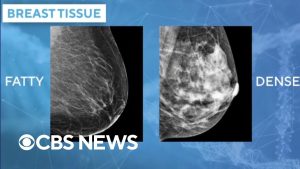

- 40 % des femmes ont des seins denses, rendant le dépistage plus complexe.

Des médias tels que CBS News rapportent que l’utilisation de l’IA dans le dépistage du cancer du sein permet d’identifier des risques que les mammographies traditionnelles pourraient manquer. Dr. Lehman souligne que l’IA peut analyser des éléments prédictifs au-delà de la densité mammaire, offrant ainsi une approche plus précise pour le dépistage.